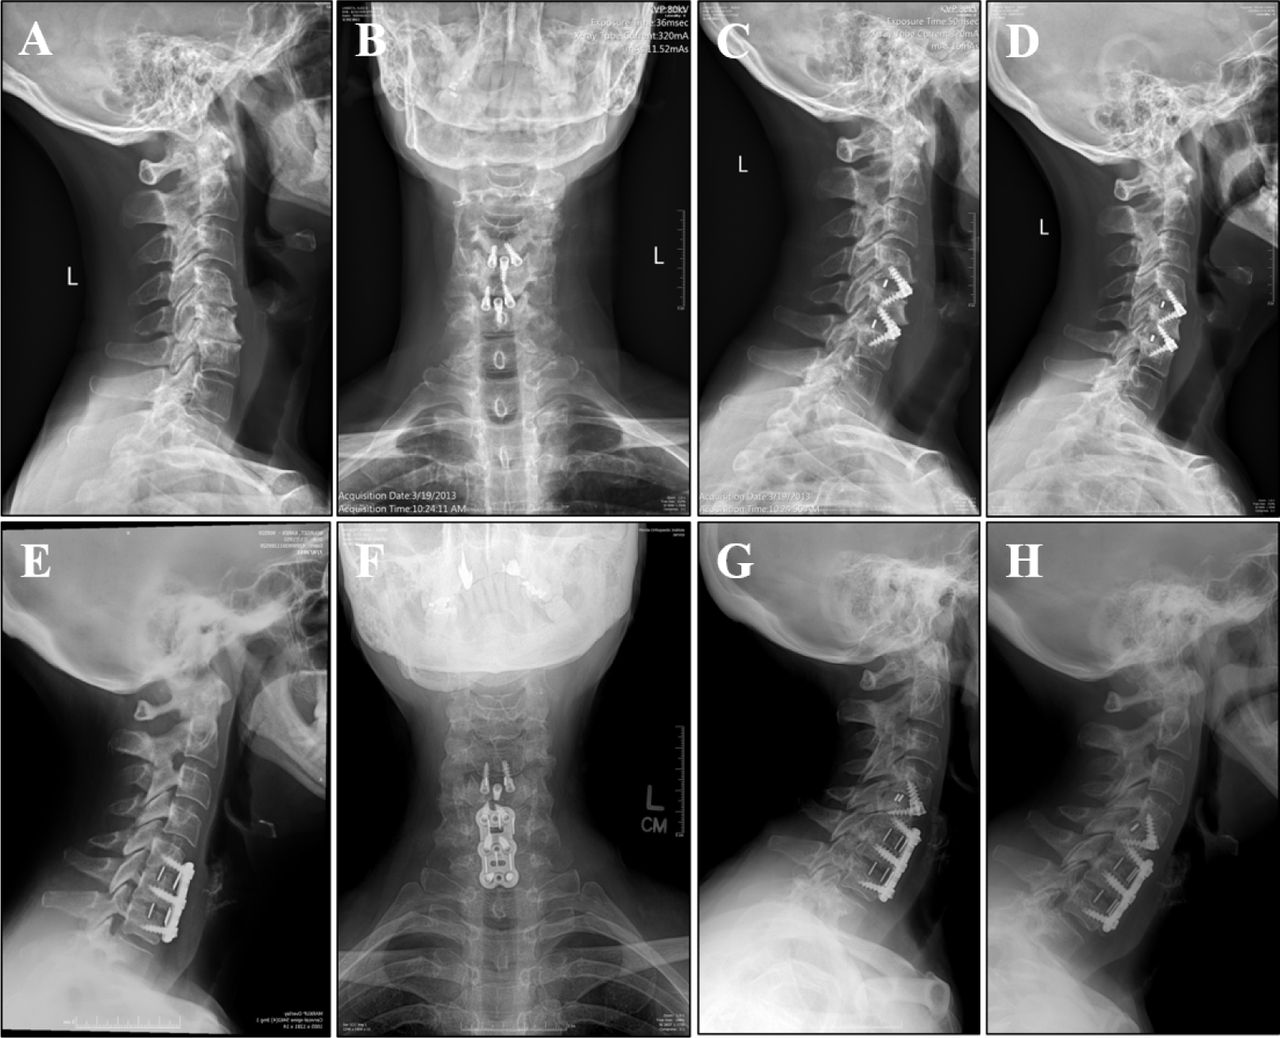

Disc Spacer Device Radiology . Knowledge of the various spinal instrumentation techniques, implants, expected postoperative findings, and related complications can help radiologists accurately interpret. As in the cervical spine, fusion consists of placement of graft material and an interbody. Current trends in spinal fusion include new surgical routes of access, the use of. They can be used in various. The appearances are varied with the. Spinal instrumentation hardware refers to various types of implants used for fixation in spinal surgery. Spacer devices are often place either in isolation or along with anterior fixation following cervical disc surgery. The procedure involves bilateral partial laminectomies followed by diskectomy. Cervical spinal fusion and instrumentation. On radiography, the bryan artificial disk consists of two metal convex shells with anterior stops, a central access port, and a radiolucent nucleus. A cervical disc replacement (also known as a spacer) is a prosthesis surgically inserted in the native disc space. Device placed in the intervertebral space to restore disc height and facilitate bone growth to promote intervertebral fusion [2, 7].

Disc Spacer Device Radiology Current trends in spinal fusion include new surgical routes of access, the use of. Device placed in the intervertebral space to restore disc height and facilitate bone growth to promote intervertebral fusion [2, 7]. They can be used in various. As in the cervical spine, fusion consists of placement of graft material and an interbody. A cervical disc replacement (also known as a spacer) is a prosthesis surgically inserted in the native disc space. Current trends in spinal fusion include new surgical routes of access, the use of. Spinal instrumentation hardware refers to various types of implants used for fixation in spinal surgery. Cervical spinal fusion and instrumentation. Knowledge of the various spinal instrumentation techniques, implants, expected postoperative findings, and related complications can help radiologists accurately interpret. The appearances are varied with the. On radiography, the bryan artificial disk consists of two metal convex shells with anterior stops, a central access port, and a radiolucent nucleus. Spacer devices are often place either in isolation or along with anterior fixation following cervical disc surgery. The procedure involves bilateral partial laminectomies followed by diskectomy.

Spinal fusionhardware construct Basic concepts and imaging review Disc Spacer Device Radiology Spinal instrumentation hardware refers to various types of implants used for fixation in spinal surgery. On radiography, the bryan artificial disk consists of two metal convex shells with anterior stops, a central access port, and a radiolucent nucleus. Device placed in the intervertebral space to restore disc height and facilitate bone growth to promote intervertebral fusion [2, 7]. They can. Disc Spacer Device Radiology.